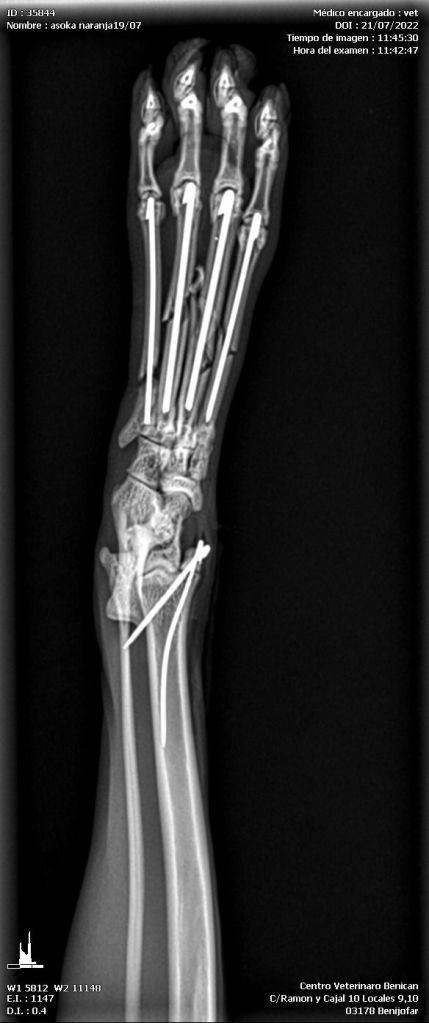

Unser Iker ist schon ein armes Kerlchen. In Spanien wurde er schwer verletzt auf der Straße gefunden. Er hatte einen Autounfall und der Fahrer ließ ihn einfach liegen. Glücklicherweise fand ihn ein lieber Mensch und brachte ihn umgehend zu einem Tierarzt. Sofort wurde er tierärztlich versorgt und geröntgt (s. Röntgenbilder und ein Bild von Iker nach OP). Er hatte einen gebrochenen Schwanz, ein gebrochenes Schienbein, und der Mittelfußknochen des linken Beines war ebenfalls gebrochen. Iker wurde operiert. Die Beinfrakturen wurden mit Nägeln stabilisiert. Der Schwanz musste leider komplett amputiert werden.